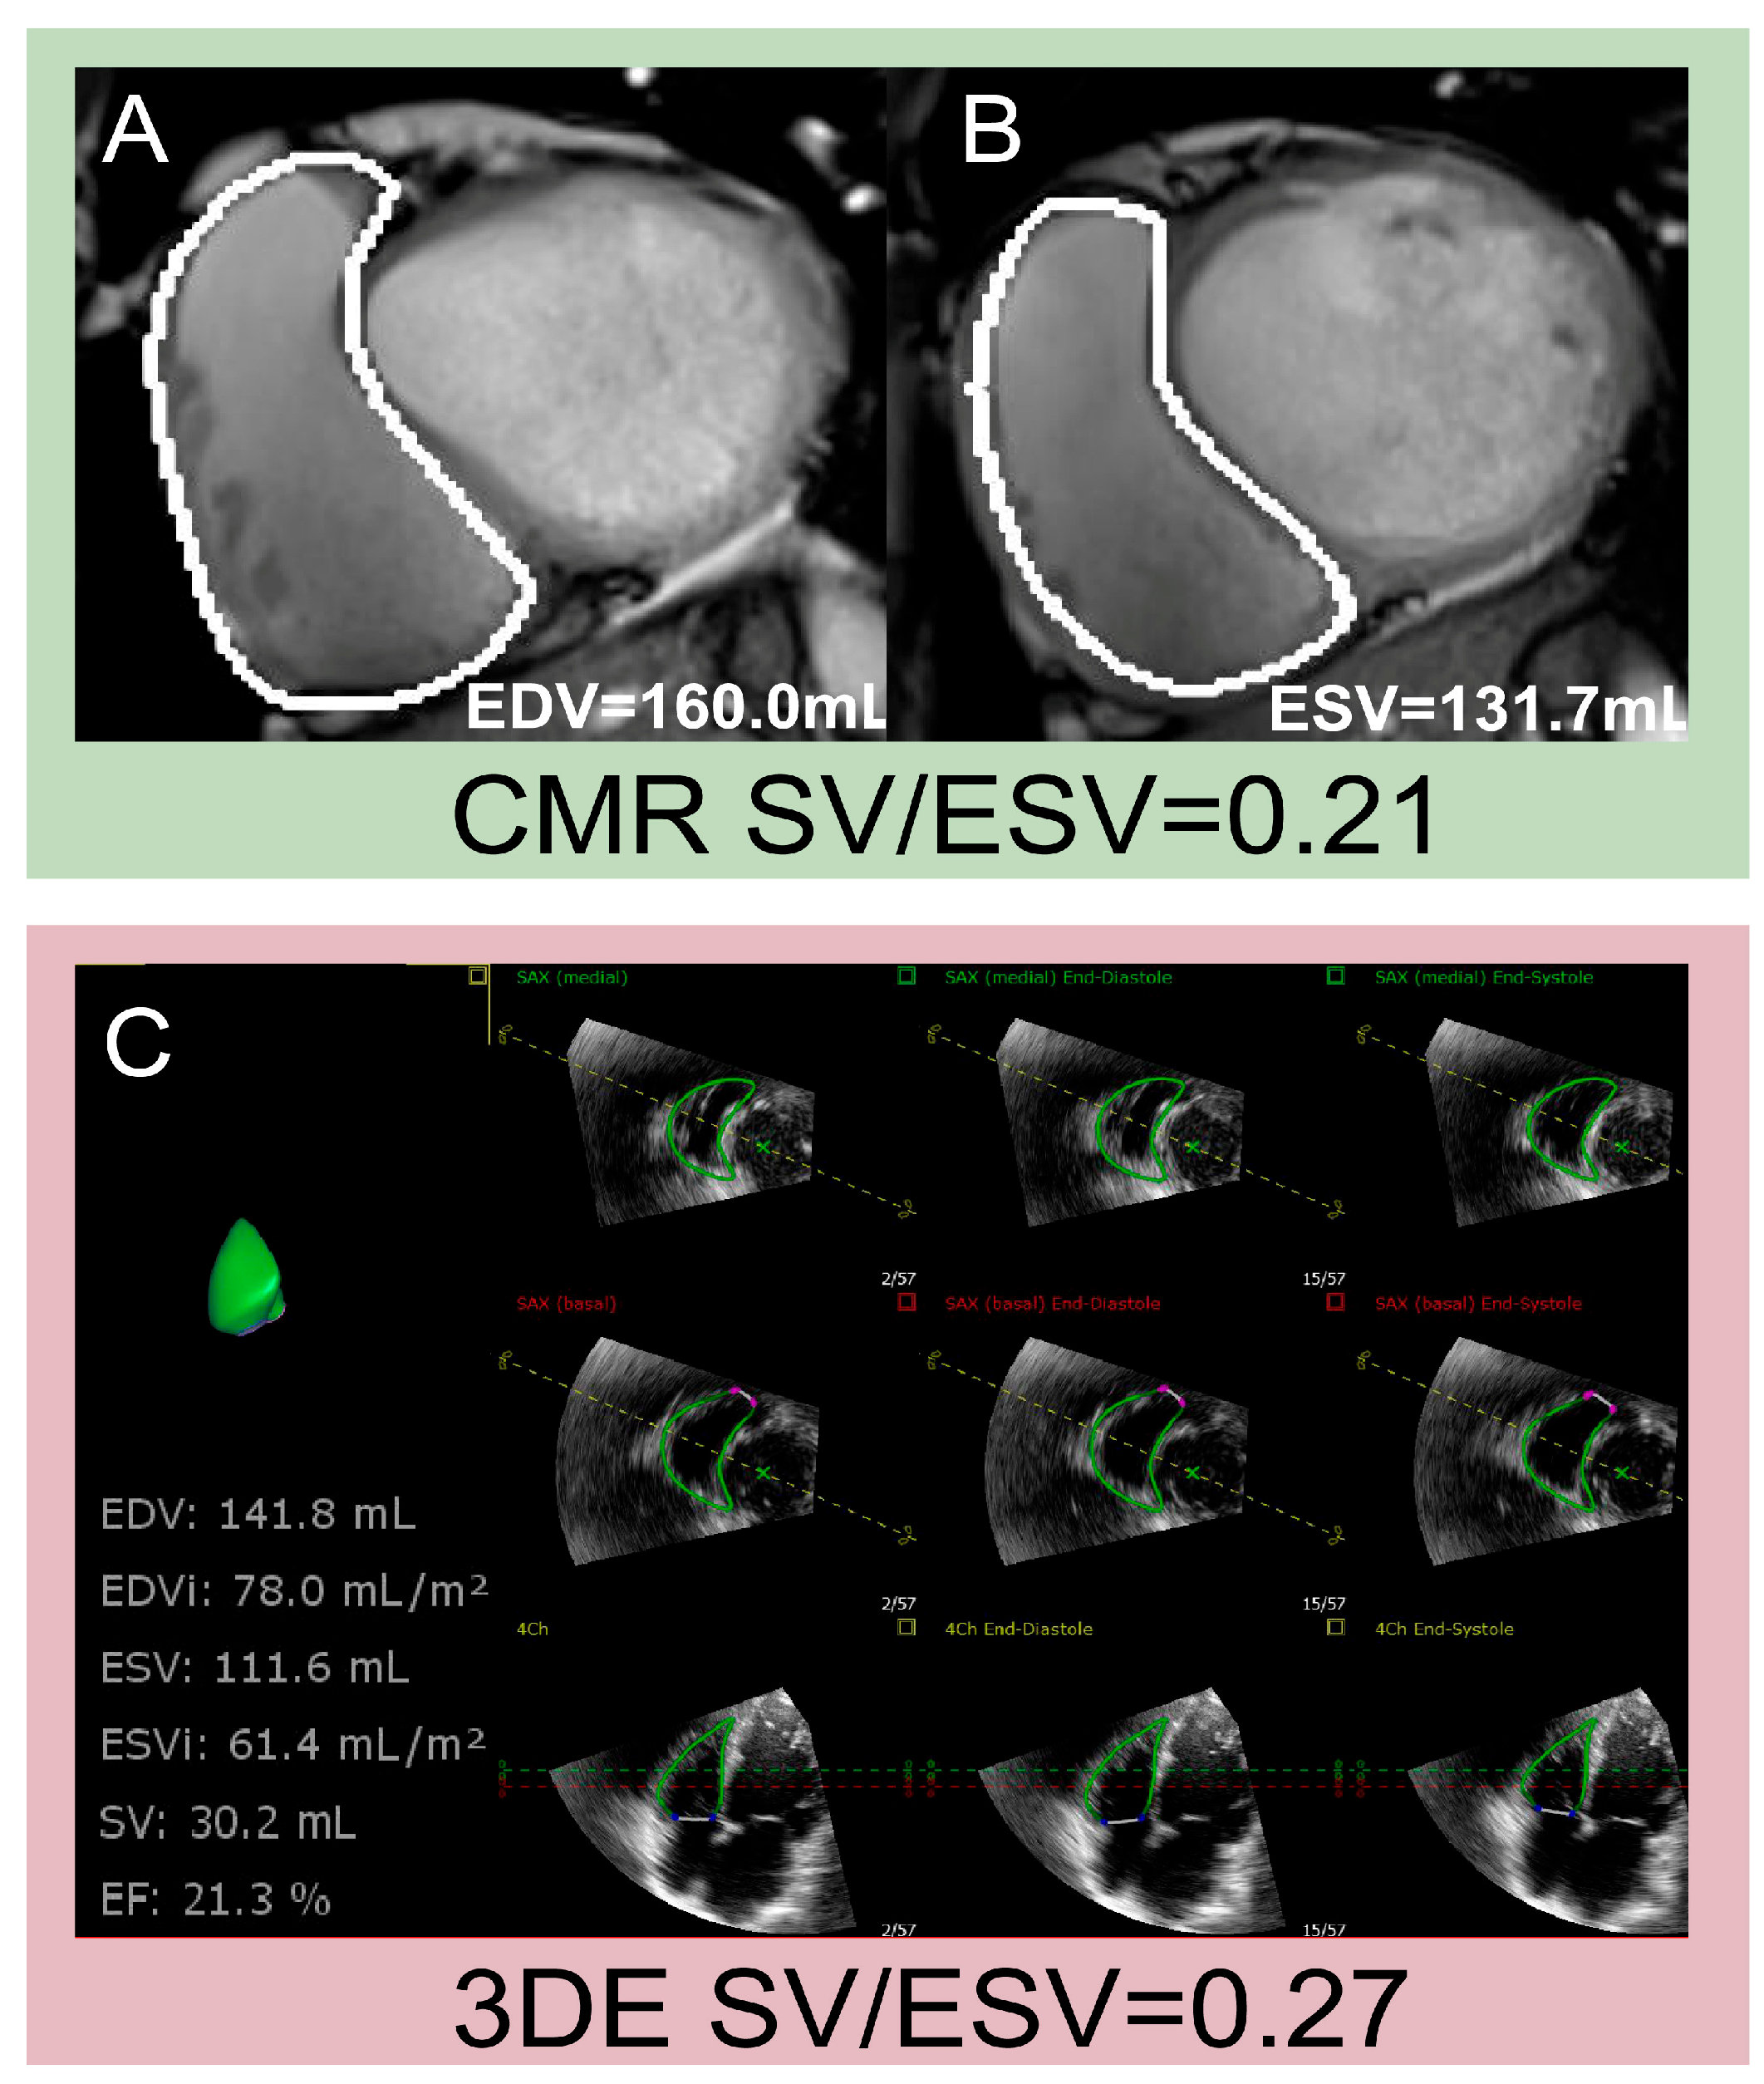

Similar to CMR, 3DE can accurately obtain volume parameters without relying on geometric assumptions of RV morphology. Additionally, 3DE-derived SV/ESV has emerged as a novel parameter of RV-PA coupling, and examples of assessments of SV/ESV using CMR and 3DE are shown in Figure 4. A strong correlation of SV/ESV with Ees/Ea has been confirmed in patients with PH [47]. A few studies have concluded that SV/ESV is a prognostic index in HFpEF and TR [45,48]. Given the limited clinical evidence on 3DE-derived RV-PA coupling in cardiovascular diseases, further studies should explore its diagnostic applicability across various conditions and compare its efficacy with that of other conventional markers. The 2025 ASE guidelines endorse echocardiographic assessments of RV-PA coupling as a valuable adjunct for enhancing risk stratification in clinical practice [49], which emphasizes the need for comprehensive evaluations of RV-PA coupling in the process of evaluating RV function.

Figure 4. Examples of assessments of SV/ESV using CMR and 3DE. (A,B) Measurement of EDV, ESV, and SV using CMR; (C) measurement of EDV, ESV and SV using 3DE. 3DE: three-dimensional echocardiography; CMR: cardiac magnetic resonance; EDV: end-diastolic volume; ESV: end-systolic volume; SV: stroke volume.